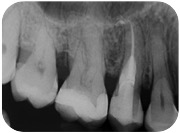

Sì, perchè ora faccio il figo, ma nel non lontano 2011, mi arriva una paziente con questo dente.

Riassorbimento esterno - rx iniziale Dutto Valentina